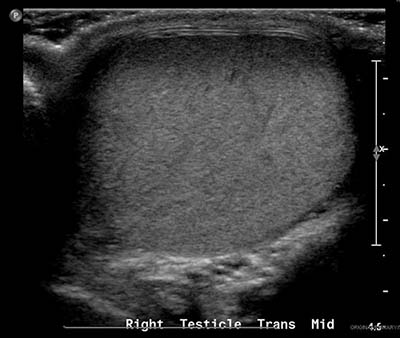

Right Testicular Mass in a 28-yo Man

Test Interpretation

Appropriate testing is done and the result of the imaging study is shown. Which of the following is a correct interpretation of the scrotal ultrasonography?